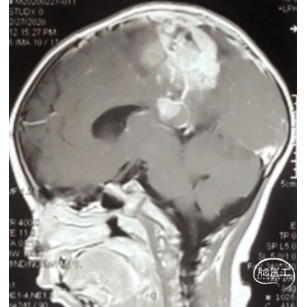

双侧额顶叶中线旁脑实质内团片状异常信号影,呈明显花环状强化,累积脑膜及胼胝体压部,性质待定,恶性胶质瘤?

本例患儿肿瘤位于双侧额顶叶,大脑镰旁,增强扫描呈明显环形强化,提示肿瘤血运丰富。患儿年龄小,体重低,相对血容量少,如何控制术中出血是手术成功的关键。而术后肢体瘫痪或瘫痪加重是手术的主要并发症,中央沟静脉损伤、胼周动脉损伤、中央沟局部皮层损伤、癫痫、血肿以及脑水肿加重是其常见原因。术前脑血管造影有助于判断肿瘤与周围血管、组织的位置关系,明确上失状窦有无闭塞,对手术的切口设计有重要的参考价值及避免术中损伤不易发现的血管及组织。

非典型畸胎瘤样/横纹肌样瘤( AT /RT) 是发生在儿童中枢神经系统的少见的具有极大侵袭性的恶性肿瘤,在儿童中枢神经系统肿瘤中发病率极低。CT平扫多表现为混杂密度,也可等或稍高密度,呈不均匀或均匀强化,瘤内常可见囊性变及瘤周低密度水肿带。MRI扫描T1加权像为低信号,T2加权像为等信号或高信号,肿瘤实质与灰质信号相似或稍高,增强扫描可见中等至明显 增强,等信号时可能与肿瘤细胞密集,细胞核比例大而含水量相对较少有关。AT /RT是原发于中枢神经系统、好发于儿童、极其少见、侵袭性极高的胚胎性肿瘤,临床表 现及影像学无特异性,确诊有赖于组织病理。最大限度的安全切除,并辅以放化疗,可改善患者预后,但总体预后仍然很差。